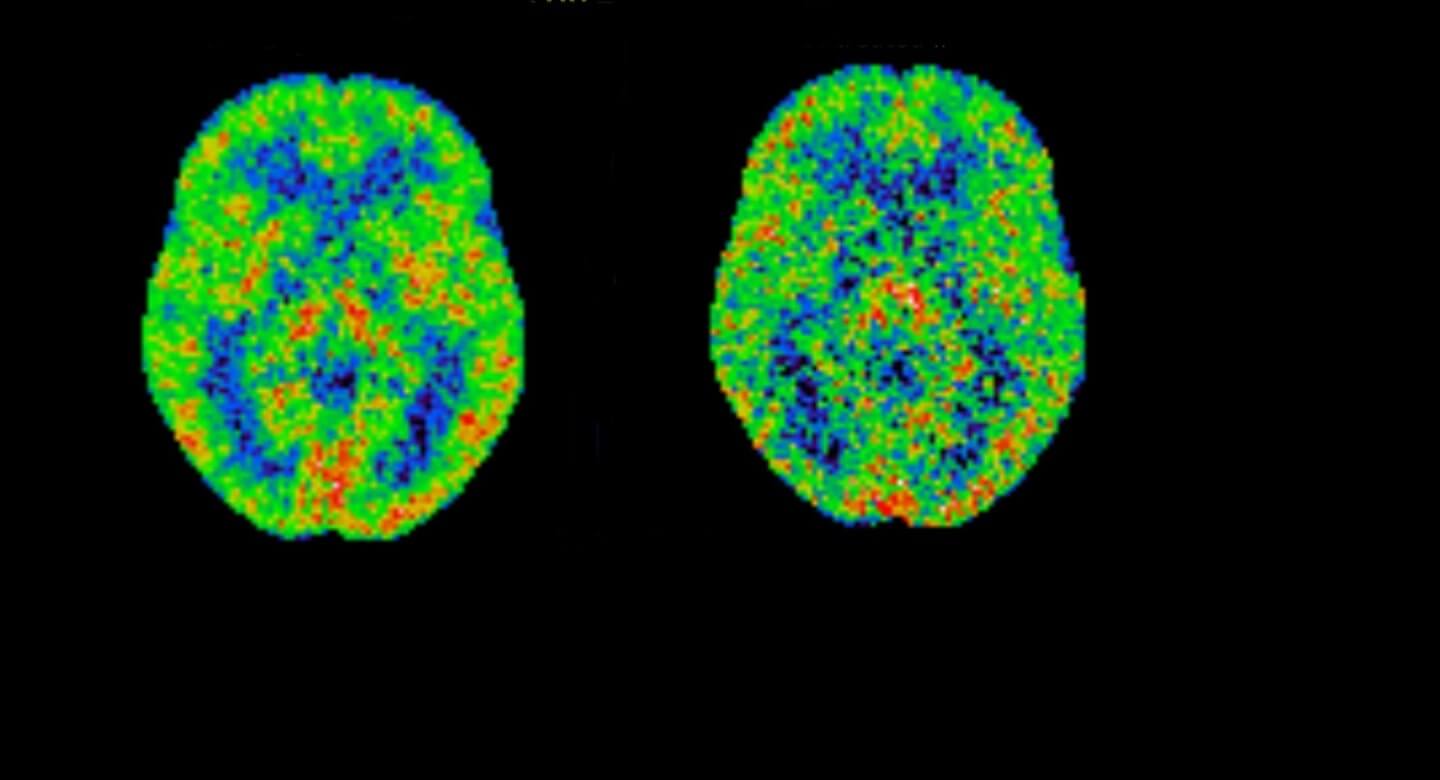

As we approach late life, new mental health concerns may emerge: memory problems, Alzheimer’s disease or dementia, and higher risks of serious side effects from psychiatric medications. CAMH researchers are aiming to prevent late-life mental illnesses altogether and to find safer, more effective treatments when they do occur.

This new way of treating agitation and aggression in people with Alzheimer’s disease is showing positive outcomes, and will be tested at seven sites across Canada.

Depression among older people may bring added challenges, including a greater risk of developing dementia. CAMH researchers are studying new treatment approaches.